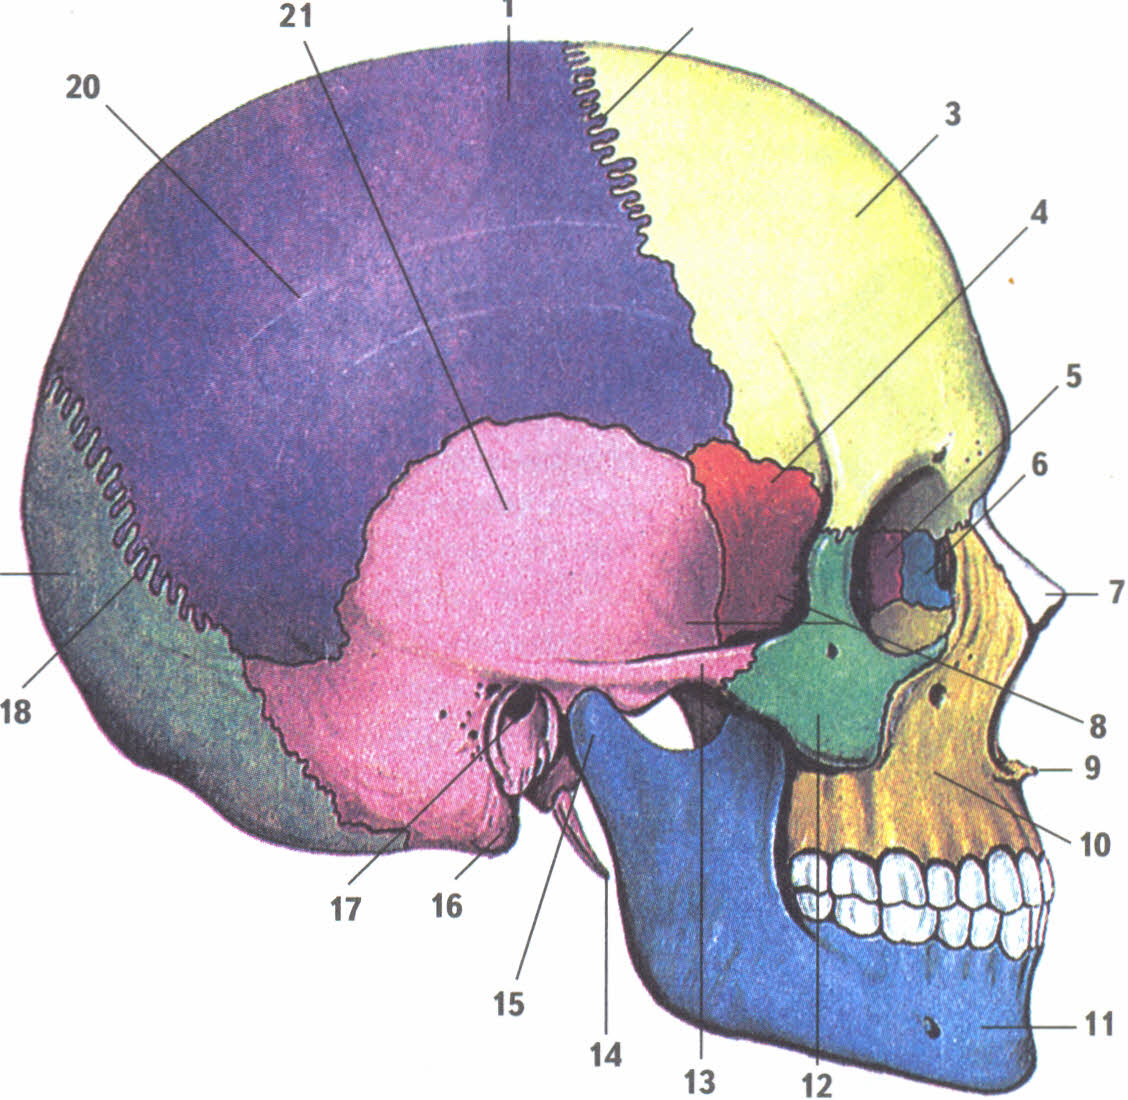

Анатомия детского черепа: Рентгеновские снимки и описание